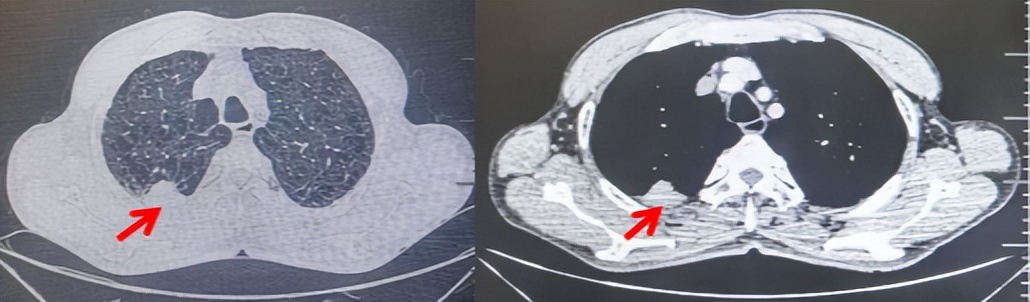

71岁男性,高血压病史20年,口服药物治疗,无糖尿病、心脏病等基础疾病,吸烟史50年,20支/天,已戒1年余,无饮酒史,无肿瘤家族史。2023.11因咳嗽、咳痰行胸CT检查:左肺下叶占位性病变,大小约12mmx8mm(如图5)。2023.11.20行“单孔胸腔镜左肺中下叶切除、肺门及纵隔淋巴结清扫、胸膜粘连松解术”;术后病理:(左肺下叶)结合免疫组化鳞状细胞癌(中、低分化),局部见脉管内癌栓,未见确切神经侵犯,(气管切缘)净。(淋巴结)未见转移癌0/19(4组0/1;5组0/1;6组0/2;7组0/1;9组0/1;10组0/2;11组0/3;12组0/2;13组0/2;14组0/4)。术后分期pT1bN0M0 IA期,术后定期复查。

2024.09.12复查胸部CT示左侧胸膜结节,大者约为27mmx13mm,考虑转移可能性大,纵隔淋巴结增大,恶性?(如图6)。患者行胸膜穿刺活检取病理,结果示(胸膜)结合免疫组化,支持鳞状细胞癌,PD-L1(克隆号28-8)TPS约20%。分期为rT0N2bM1a IVA期,DFS为10个月。2024.09.24起行替雷利珠单抗联合紫杉醇+卡铂方案治疗4周期,复查胸CT评效SD(如图7)。后患者因脑梗塞停止治疗,于综合医院就诊,后未返院复查及治疗。

图5:患者手术前(2023.11)胸部CT肺窗及纵隔窗

图6:患者胸膜及纵隔转移(2024.09)胸部CT肺窗及纵隔窗

图7:替雷利珠单抗联合白蛋白紫杉醇+卡铂治疗4周期后(2024.12)胸部CT肺窗及纵隔窗